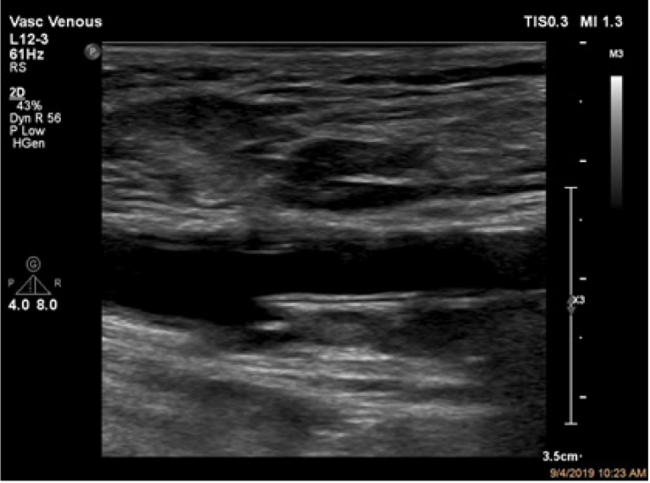

Technique. All patients underwent ultrasound-guided antegrade percutaneous access of the proximal superficial femoral artery utilizing a micropuncture access needle and wire. Meticulous care was taken to ensure a 12 o’clock arteriotomy at a 45° angle using ultrasound guidance in both the transverse and longitudinal projections. In the longitudinal projection, the proximal superficial femoral artery was visualized just after the common femoral bifurcation and the soft tissue was inspected. After the needle was introduced intra-arterially, the wire was passed under ultrasound guidance to ensure a luminal course and then under fluoroscopic guidance to ensure an antegrade path without resistance or deviation (Figure 1). Diagnostic angiography was obtained through the 5 Fr sheath and then upsized to either a 6 Fr or 7 Fr sheath to accommodate the intervention planned.

MynxGrip- or MynxControl-assisted closure of the percutaneous access arteriotomy was performed upon conclusion of the intervention. Heparin was reversed to ensure an activated clotting time (ACT) of <180 seconds and a systolic blood pressure <180 mm Hg. The appropriately sized device was used for the size of access arteriotomy, with either a 5 Fr or 6-7 Fr Mynx device. The Mynx device balloon was prepped before use with a 50:50 contrast-to-saline ratio. Next, the Mynx device was introduced and the balloon was inflated under ultrasound guidance. Then, the device and the sheath were slowly retracted to the arteriotomy site under constant ultrasound visualization. Excellent resolution of the balloon location within the vessel can be obtained, as shown in Figure 2. When intraluminal anterior wall apposition of the balloon was seen on ultrasound, the polyethylene glycol plug was deployed. This wall apposition of the balloon prevents inadvertent intra-arterial polyethylene glycol introduction. Tension was held and then the plug was released per the device instructions for use (IFU). Following the requisite deployment steps, additional ultrasound-guided pressure over the arteriotomy site and sheath tract was performed for 5 minutes. At that time, duplex ultrasonography was performed to evaluate for evidence of hematoma formation, active bleeding, or pseudoaneurysm formation.